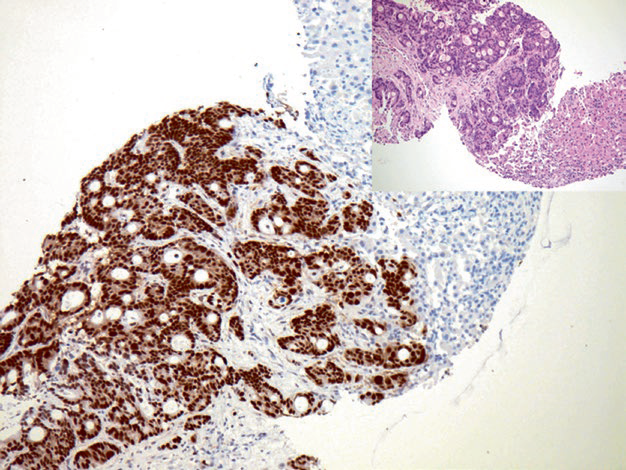

Figure 1. Metastatic colorectal adenocarcinoma, with strong nuclear positive expression of CDX-2 in tumor cells.

Positive expression pattern: Nuclear

Recommended positive control tissue: Appendix